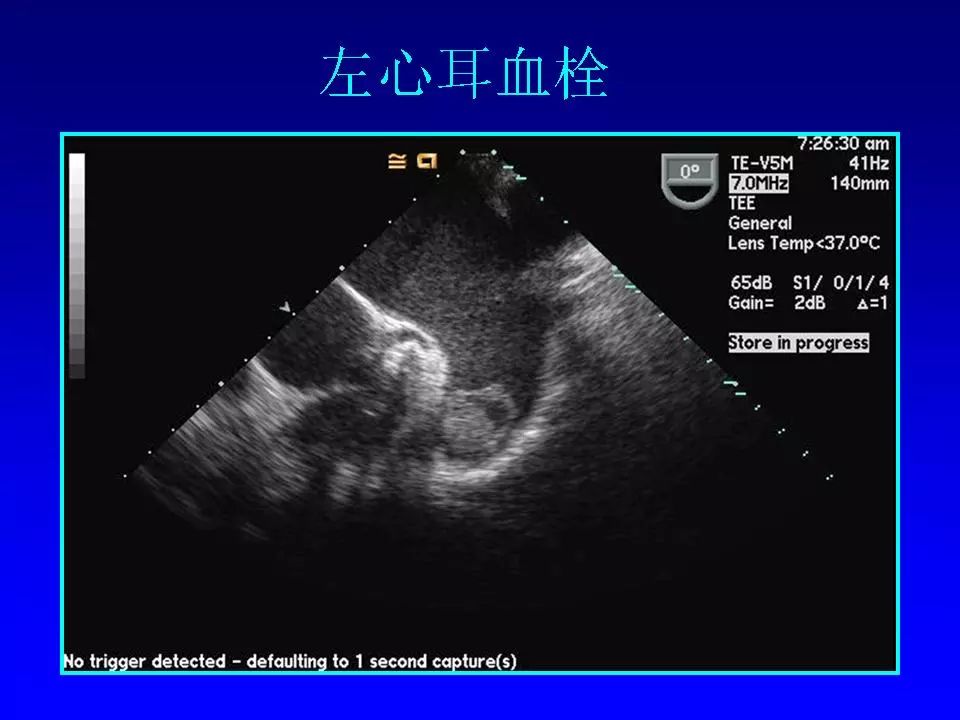

在2018老年冠心病学习班上,阜外医院心律失常中心的方丕华教授从房颤的分类、治疗策略和介入治疗方法入手,与大家分享了房颤介入治疗技术的个体化应用策略